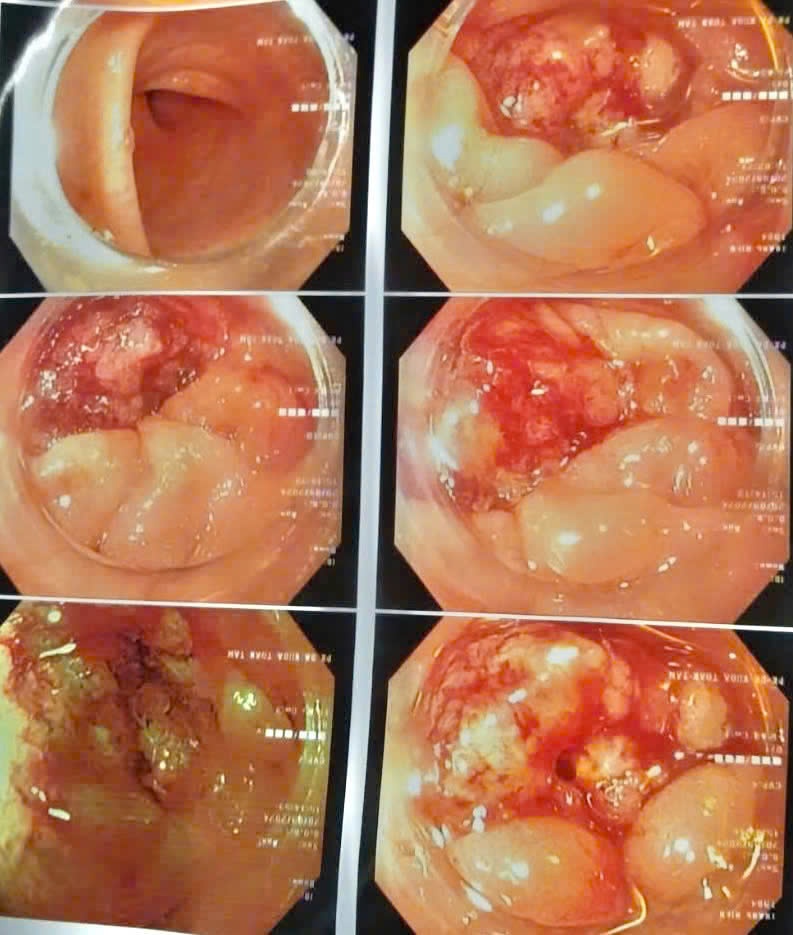

Hình ảnh tổn thương sùi loét đại tràng qua nội soi. Ảnh: BVCC. |

Kết quả chụp CT Scanner ổ bụng và nội soi đại trực tràng cho thấy xuất hiện nhiều hạch mạc treo đại tràng trái, tổn thương sùi loét đại tràng trái chiếm gần hết chu vi lòng trực tràng.

Cô gái được các bác sĩ chẩn đoán mắc ung thư biểu mô tuyến đại tràng trái có biến chứng bán tắc ruột.